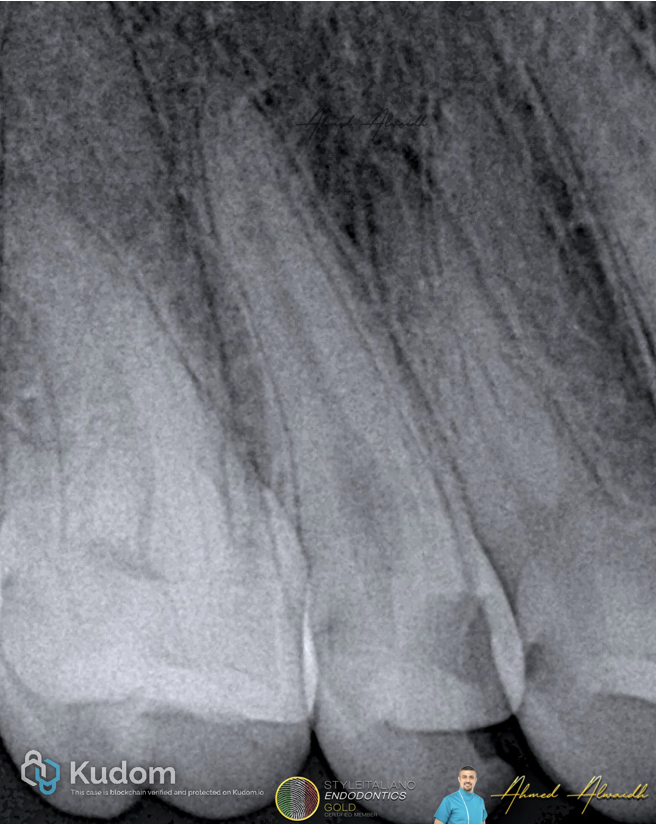

Fig. 3

Post obturation IOPA showing 3D obturation of the root canal system filling the two POEs